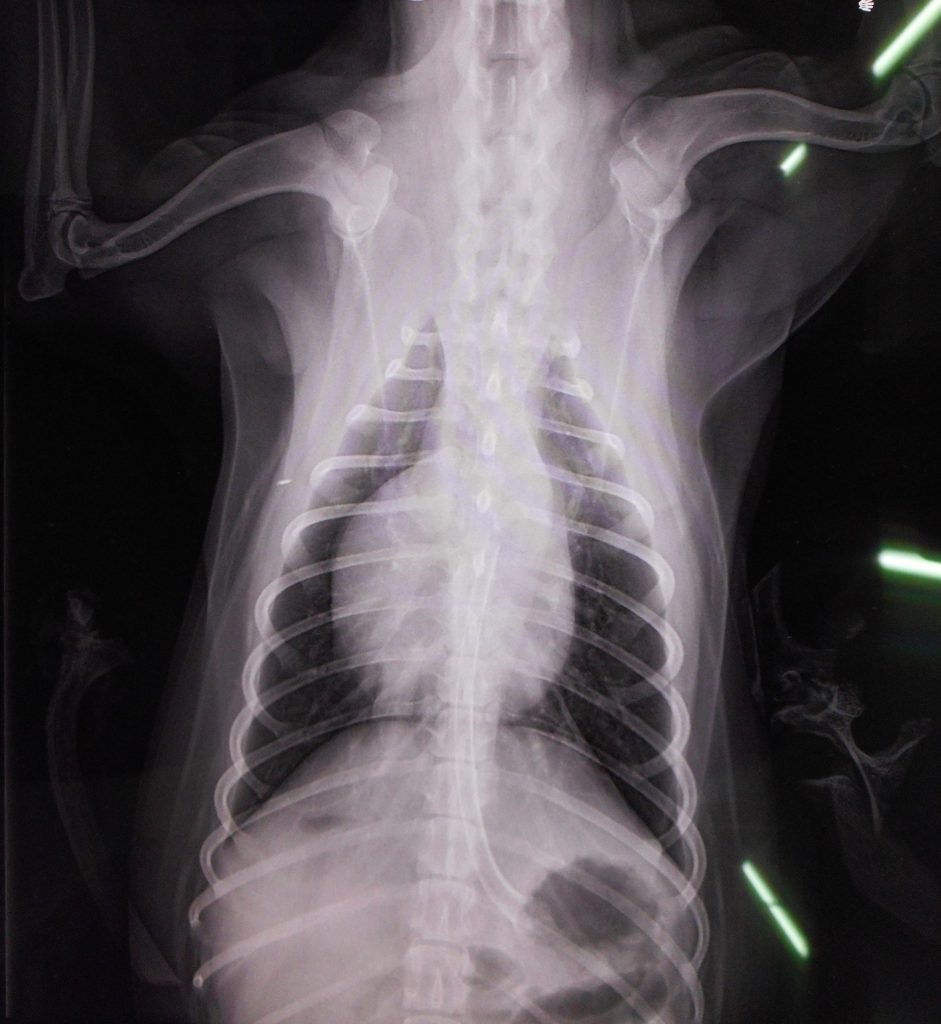

レントゲン検査です

どこにあるかわかりますか?

横にうっすら写っているのが比較のための鹿の骨

ありましたね🦴

診断:食道・胃に鹿骨閉塞

かなりの大きさで長さがある

いつものようには吐かせられぬ

胃内視鏡決定